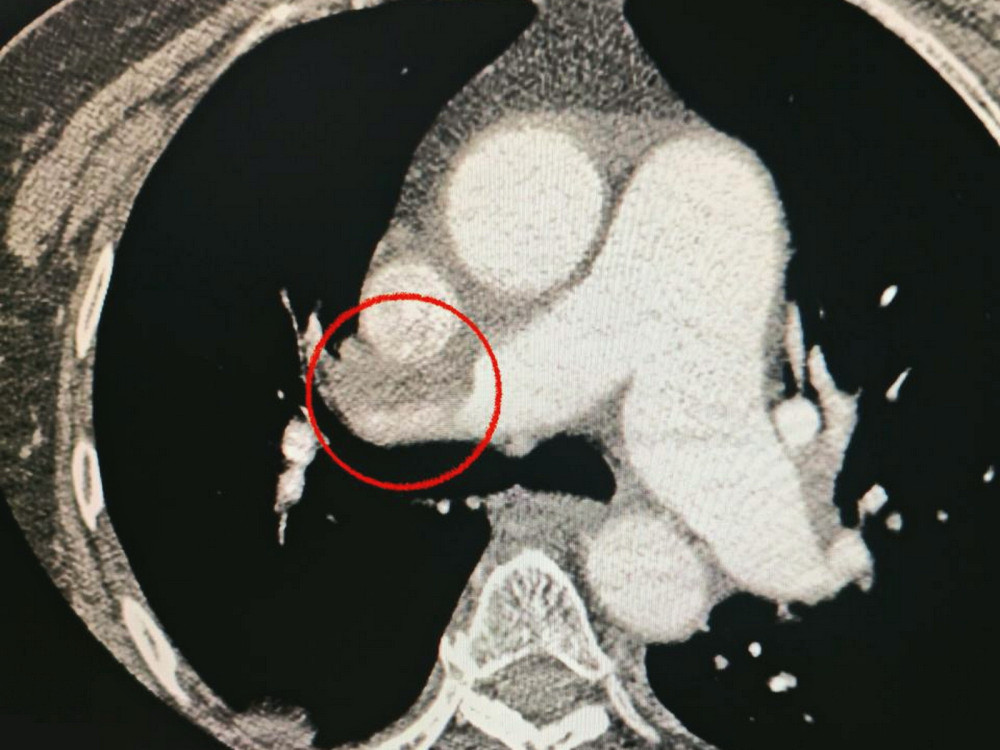

Пациентка поступила в больницу с тяжелым острым инсультом. При проведении компьютерной томографии врачи обнаружили закупорку средней мозговой артерии.

Кроме того, врачи заметили, что пациентка испытывает трудности с дыханием, поэтому провели дополнительное обследование легких. Установлен диагноз тромбоэмболии легочной артерии.